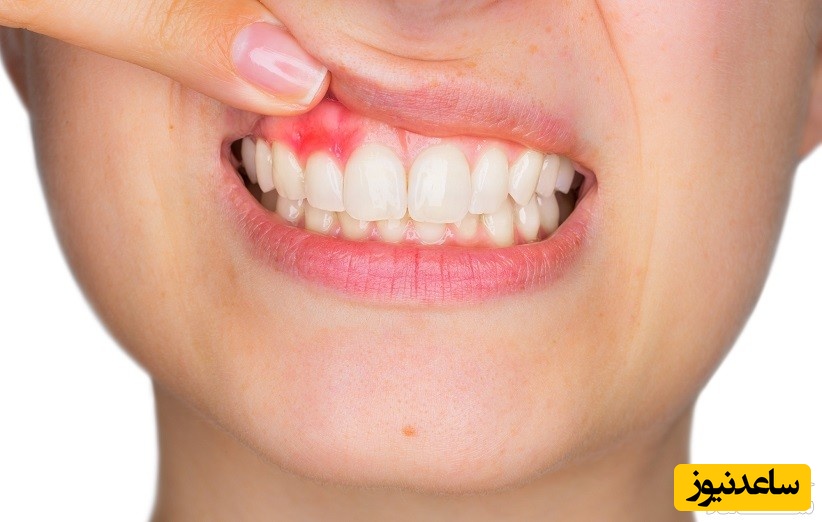

به گزارش سرویس سلامت ساعدنیوز، در طول زمان، بیماری لثه سبب جدا شدن از لثه دندان شده و در نهایت باعث ایجاد فاصله بین دندان ها و لثه می گردد. جرم در فواصل بین دندان ها و لثه تشکیل شده و باعث ضعیف شدن استخوان های اطراف دندان می شود. بیماری لثه، بیماری شایعی است. بسیاری از افراد در مراحل اولیه این بیماری به سر می برند که با مراقبت های صحیح دهان و دندان قابل درمان هستند اما اگر به بیماری لثه اهمیت داده نشود می تواند باعث تحلیل استخوان فک شده و نهایتاً منجر به از دست دادن دندان ها شود. در حالی که لثه بیمار قرمز، شل و به راحتی خونریزی میکند، به طوری که ممکن است هنگام خواب خون روی بالش ریخته شود و گاهی لثه دچار افزایش حجم می شود ایجاد بوی دهان می کند.

لثه های قرمز، پف کرده یا نازک می توانند نشانه ورم لثه باشند. جهت جلوگیری از پیشرفت التهاب لثه حائز اهمیت است که آن را درمان کنید. شکل جدی تر بیماری لثه باعث می شود لثه ها از دندان عقب نشینی کنند و شکل کیسه ای را پیدا کند که آلوده شده است.